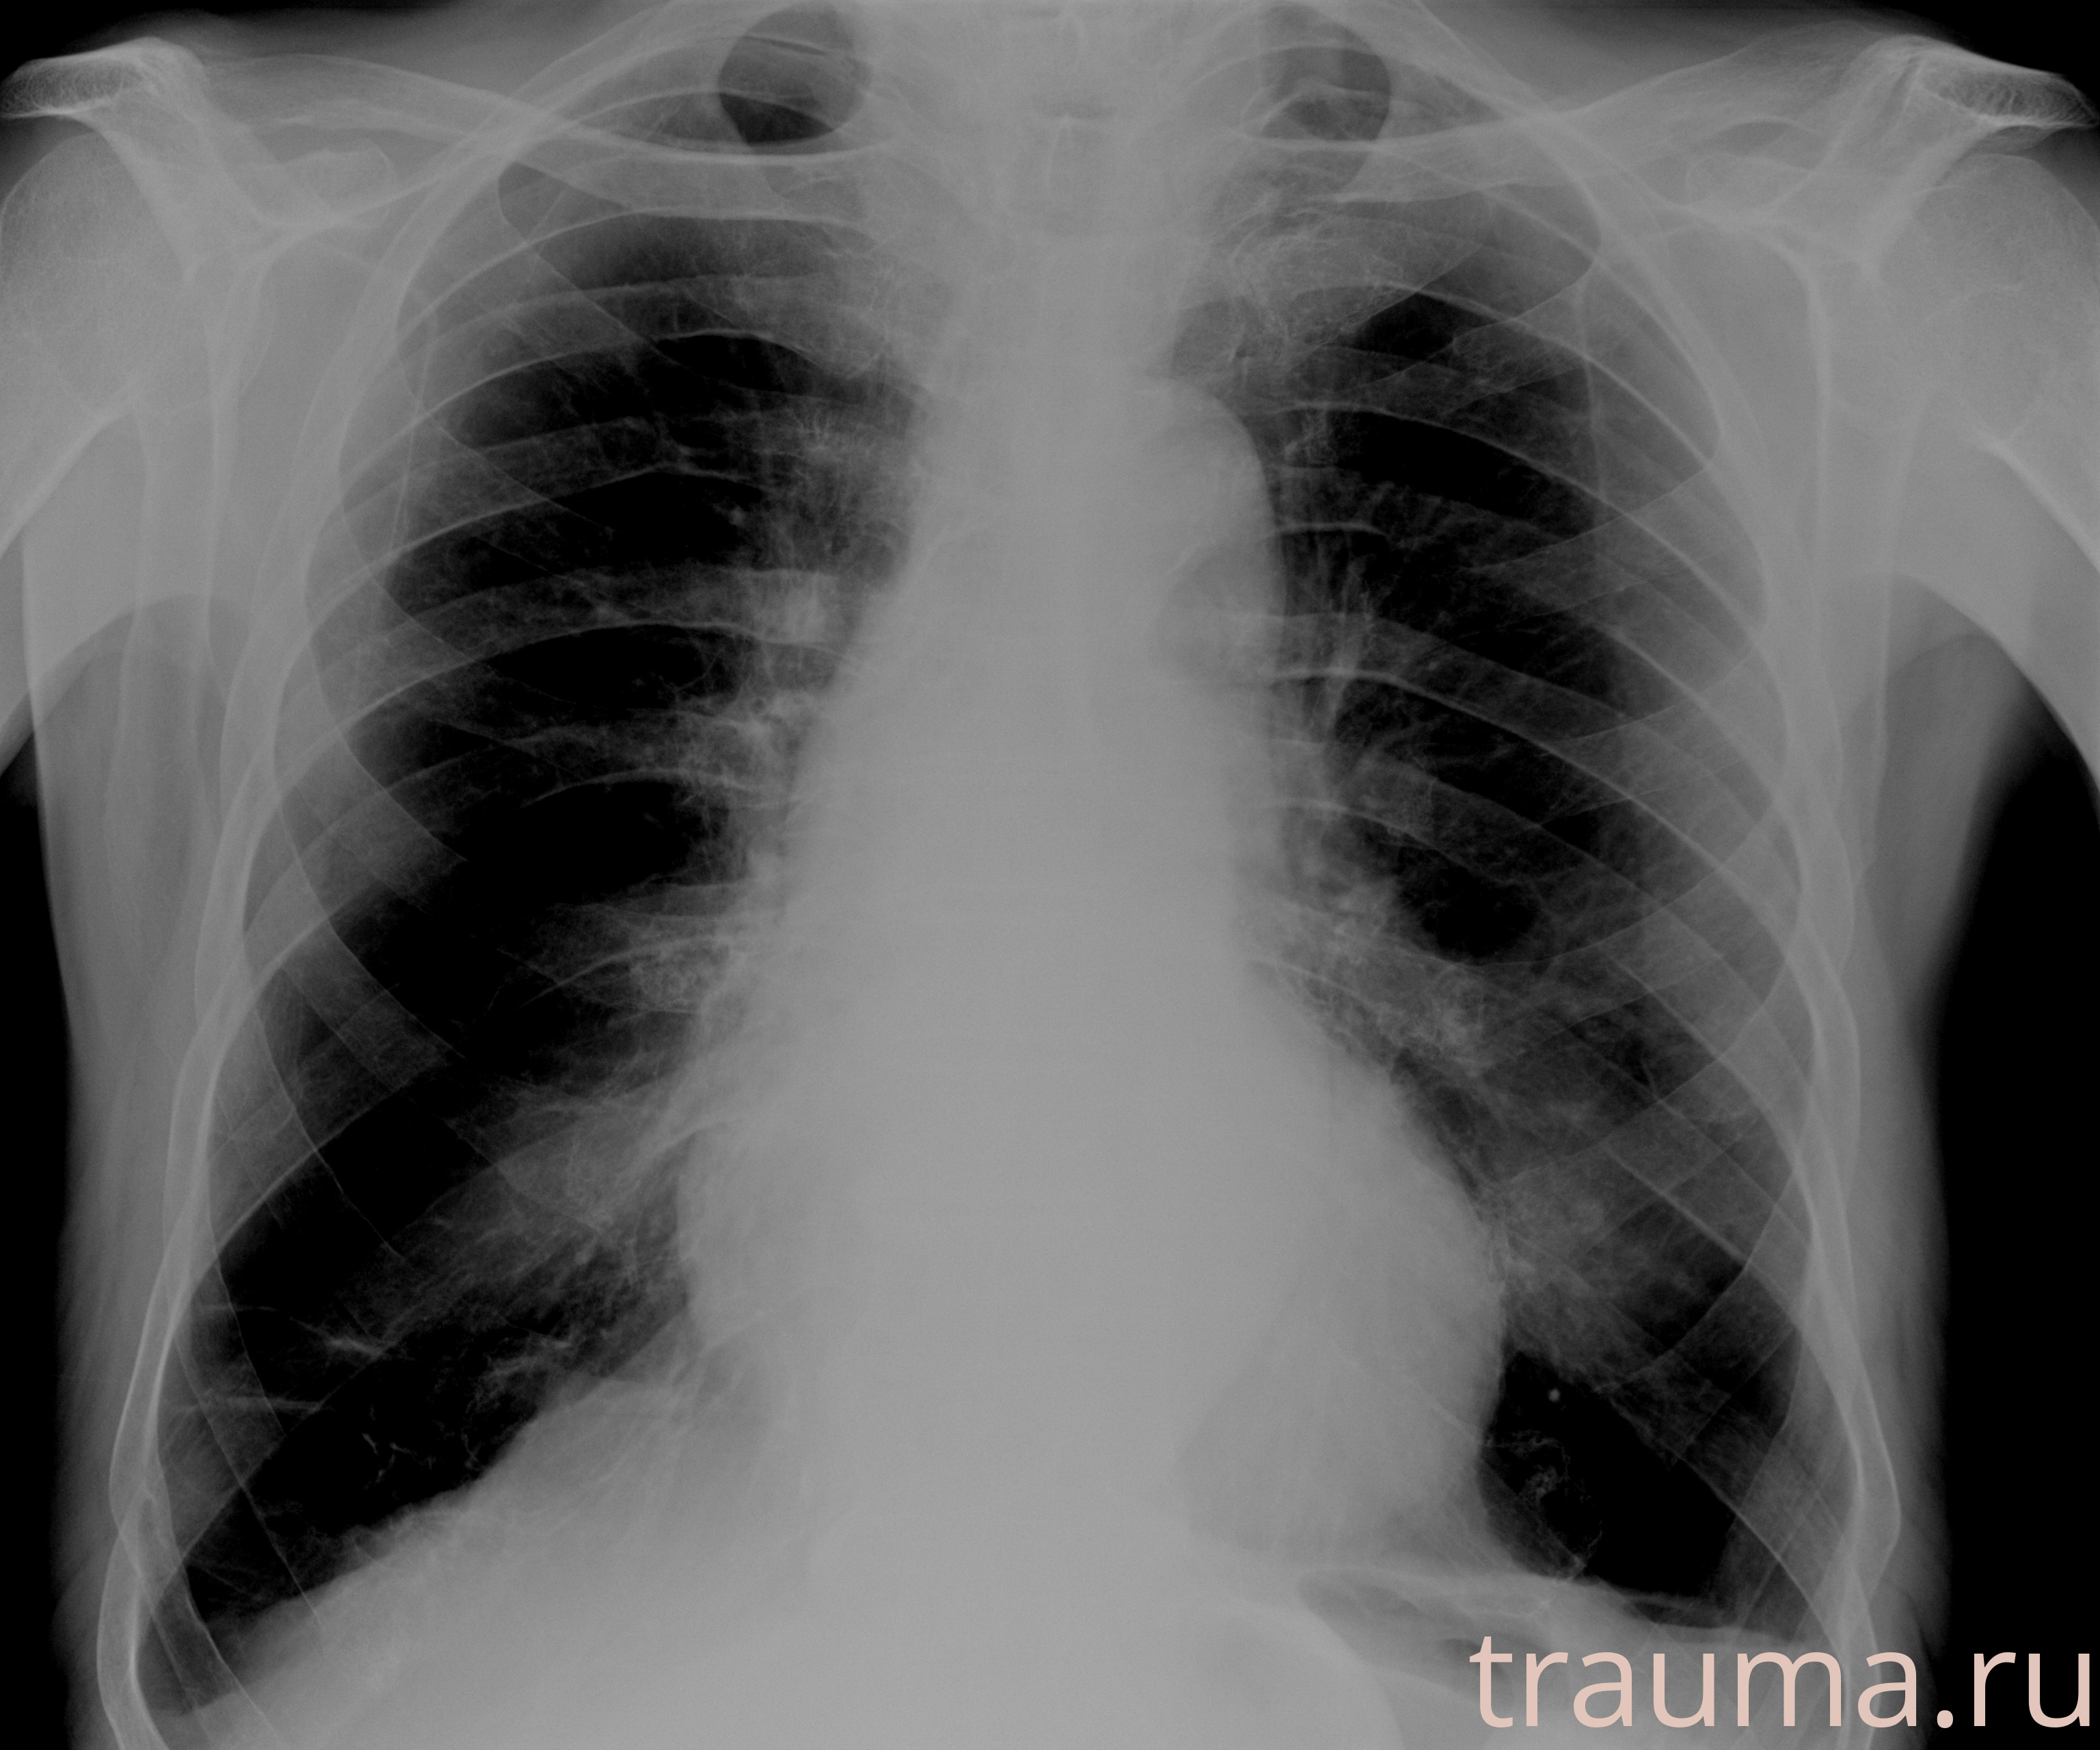

Рентгенограммы

Рентген на дому: по вашему адресу приезжает врач-рентгенолог, травматолог-ортопед с мобильным рентгеновским аппаратом, проводит диагностику травмы или заболевания, делает необходимые рентгенограммы, дает рекомендации по дальнейшему лечению. Получить качественные снимки в домашних условиях возможно благодаря уникальной методике, разработанной МосРентген Центром для института  Склифосовского